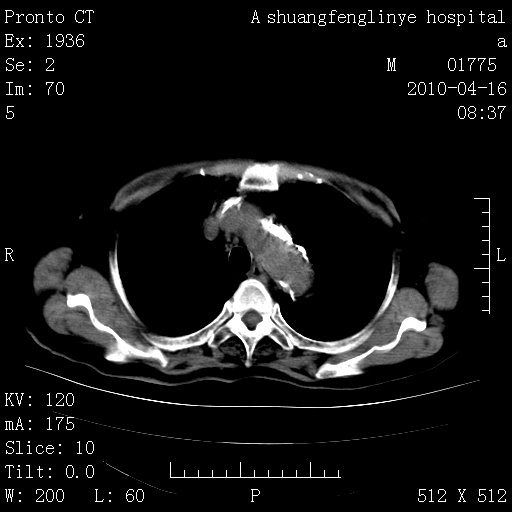

标题: CT25784:咳痰、请会诊!结核? [打印本页]

标题: CT25784:咳痰、请会诊!结核?

陈旧性结核,胃腔扩大,脾脏受压后移

慢支肺气肿,左上陈旧性结核,主动脉冠脉钙化

典型 夹层动脉瘤。 内膜瓣钙化移位

1)左肺上叶结核(纤维、增殖病灶)。2)冠状动脉及主动脉钙化。

1)左肺上叶结核(纤维、增殖病灶)。2)冠状动脉及主动脉钙化。肺动脉高压